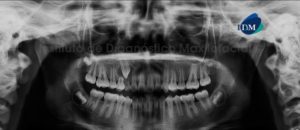

Paciente femenino de 76 años de edad es referido al Instituto de Diagnóstico Maxilofacial (IDM) para evaluación general por presentar enfemedad periodontal avanzada. A la